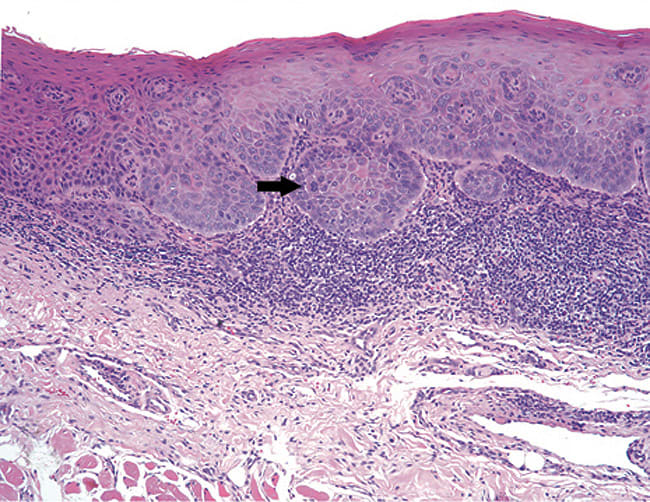

Oral epithelial dysplasia and carcinoma-in-situ

A microscopic diagnosis of epithelial dysplasia means that there are cytologic and/or epithelial architectural abnormalities. A diagnosis of dysplasia will be assigned a category—either mild, moderate or severe.16 Mild epithelial dysplasia is limited to the lower one-third of the epithelial thickness (Figure 7). Moderate epithelial dysplasia is more than one-third but less than two thirds of the epithelial thickness (Figure 8). Severe epithelial dysplasia involves more than two-thirds of the epithelial thickness (Figure 9), while carcinoma-in-situ means that the entire thickness of the epithelium is abnormal (Figure 10), although the malignant cells have not yet become locally invasive. Complicating the prediction of which lesions will undergo malignant transformation, dysplastic lesions may become invasive OCSCC without first exhibiting severe epithelial dysplasia or full-thickness carcinoma-in-situ. In a meta-analysis of pooled data from 992 patients, malignant transformation rate for mild to moderate dysplasia is estimated at 10.3%, while the malignant transformation rate of moderate to severe dysplasia is 24.1%.17